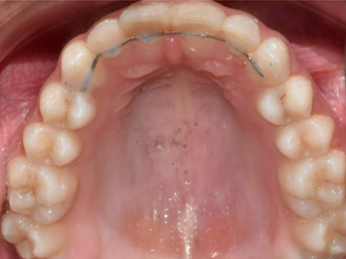

Hẹp cung hàm

Cung hàm hẹp là tình trạng chiều rộng ngang của cung hàm trên và/hoặc cung hàm dưới quá hẹp khiến răng không thể thẳng hàng và tiếp xúc khớp cắn tốt.

Lựa chọn điều trị Invisalign: Invisalign Comprehensive

Năm: 2022

Mức độ khó: Nâng cao

Giới tính: Nữ